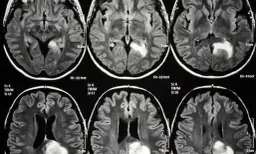

Miażdżyca to choroba, która może prowadzić do szeregu psychicznych objawów, wynikających z niedokrwienia i niedotlenienia mózgu. Najczęściej występującymi problemami są trudności z pamięcią i koncentracją. Pacjenci często zauważają, że mają problemy z przyswajaniem nowych informacji oraz zapominają bieżące wydarzenia. Te objawy mogą być nie tylko frustrujące, ale także wpływają na codzienne życie i wykonywanie zadań.

W początkowych stadiach choroby, objawy mogą być dyskretne, na przykład mogą występować dziury w pamięci czy zmęczenie psychiczne. W miarę postępu miażdżycy, problemy te mogą się nasilać, co prowadzi do dalszych komplikacji. Dlatego tak ważne jest, aby rozpoznać i zrozumieć te objawy, ponieważ mogą one wskazywać na poważne problemy zdrowotne, które wymagają interwencji.

Problemy z pamięcią są jednym z najwcześniejszych sygnałów miażdżycy. Pacjenci często doświadczają krótkotrwałej utraty pamięci, co może objawiać się zapominaniem imion, dat czy niedawno przeczytanych informacji. Tego rodzaju problemy mogą być mylone z naturalnym procesem starzenia się, jednak w przypadku miażdżycy są one wynikiem ograniczonego przepływu krwi do mózgu.

Ważne jest, aby zwrócić uwagę na te symptomy, ponieważ mogą one prowadzić do poważniejszych problemów, takich jak otępienie naczyniopochodne. Wczesna diagnoza i interwencja mogą pomóc w spowolnieniu postępu choroby i poprawie jakości życia pacjenta.